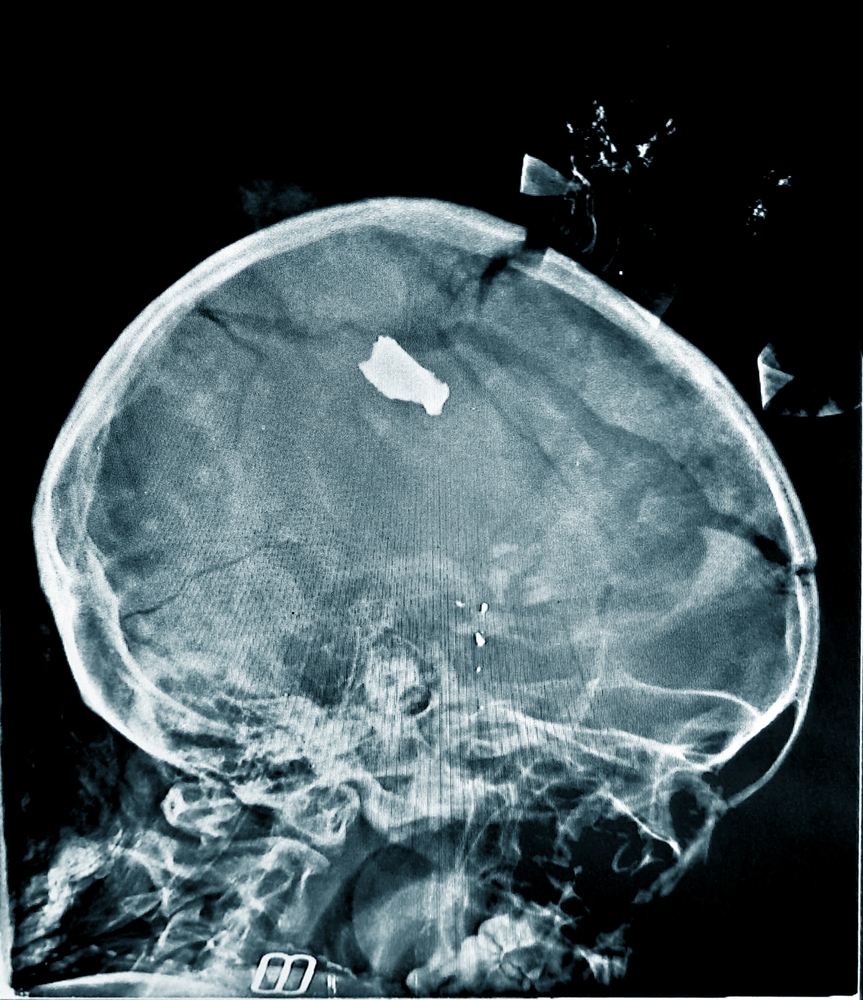

While shopping with her mother at a nearby market this 20-month-old toddler was struck by shrapnel after a bomb-blast tore through the neighbourhood. Along with other casualties the unnamed girl was brought to the Bashair Training Hospital in South Khartoum. During the Xray a part of the girls skull cap fell onto the table. An MSF emergency team operated on the girl and managed to save her life. Photographer: MSF | Location: Sudan | Date: 07/11/2024

While shopping with her mother at a nearby market this 20-month-old toddler was struck by shrapnel after a bomb-blast tore through the neighbourhood. Along with other casualties the unnamed girl was brought to the Bashair Training Hospital in South Khartoum. During the Xray a part of the girls skull cap fell onto the table. An MSF emergency team operated on the girl and managed to save her life. Photographer: MSF | Location: Sudan | Date: 07/11/2024 Nyala Teaching Hospital, Destruction. Photographer: Abdalla Berima | Location: Sudan | Date: 05/09/2024